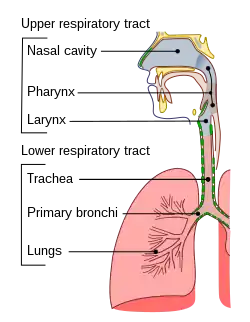

The respiratory tract is the subdivision of the respiratory system involved with the process of respiration in mammals.[1] The respiratory tract is lined with respiratory epithelium as respiratory mucosa.[2]

Air is breathed in through the nose to the nasal cavity, where a layer of nasal mucosa acts as a filter and traps pollutants and other harmful substances found in the air. Next, air moves into the pharynx, a passage that contains the intersection between the oesophagus and the larynx. The opening of the larynx has a special flap of cartilage, the epiglottis, that opens to allow air to pass through but closes to prevent food from moving into the airway.

From the larynx, air moves into the trachea and down to the intersection known as the carina that branches to form the right and left primary (main) bronchi. Each of these bronchi branches into a secondary (lobar) bronchus that branches into tertiary (segmental) bronchi, that branch into smaller airways called bronchioles that eventually connect with tiny specialized structures called alveoli that function in gas exchange.

The respiratory tract is divided into the upper airways and lower airways. The upper airways or upper respiratory tract includes the nose and nasal passages, paranasal sinuses, the pharynx, and the portion of the larynx above the vocal folds (cords). The lower airways or lower respiratory tract includes the portion of the larynx below the vocal folds, trachea, bronchi and bronchioles. The lungs can be included in the lower respiratory tract or as separate entity and include the respiratory bronchioles, alveolar ducts, alveolar sacs, and alveoli.[3]

The lower respiratory tract or lower airway is derived from the developing foregut and consists of the trachea, bronchi (primary, secondary and tertiary), bronchioles (including terminal and respiratory), and lungs (including alveoli).[8] It also sometimes includes the larynx.

The lower respiratory tract is also called the respiratory tree or tracheobronchial tree, to describe the branching structure of airways supplying air to the lungs, and includes the trachea, bronchi and bronchioles.[9]